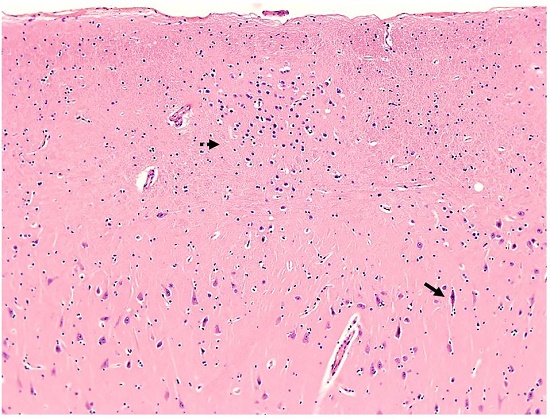

The right lung weighed 415 g (RR; 360-570 g) and showed atelectasis and congestion in the upper lobe. Microscopically, the right pleura appeared markedly thickened with granulation tissue, fibrosis, fibrin deposition, and focal acute inflammation. The left lung weighed 275 g (RR; 325-480 g) and appeared shrunken with atelectasis and congestion in the lower lobe. There was no evidence of pulmonary thromboemboli. The brain weighed 1530 g (RR; 1100-1700 g) and showed signs of mild hypoxic-ischemic damage as well as a focus of neuronal heterotopia in the hippocampus (Figure 6).

Unexpectedly, a focus of neuronal heterotopia was identified during routine microscopic examination of the hippocampus in association with neurons depicting hypoxic/ ischemic damage (i.e. “red dead neurons”) as shown in Figure 6. Of interest, central nervous system disorders and epilepsy can accompany EDS.14,15 Structural abnormalities of the central nervous system appear to be the cause of seizures. It has been suggested that seizures may originate in areas of heterotopic neurons. Abnormal neuronal positioning in VEDS can be related to defects in extracellular matrix and disruption in cellular adhesion affecting neuronal migration.14 There is no apparent correlation between the extent and severity of the neuronal heterotopia and frequency of seizures. Despite the presence of neuronal heterotopia, our patient did not have a history of epilepsy or seizures. Therefore, the significance of this finding is unknown and requires further investigation.